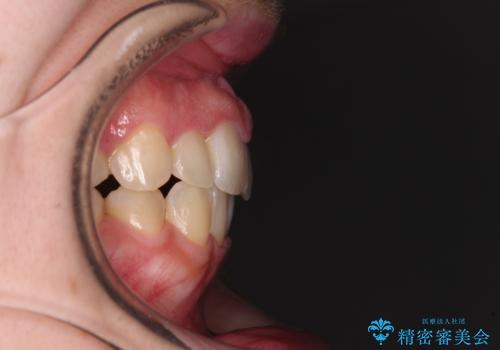

- 右上の八重歯と、左下八重歯を抜いてしまったことを気にして来院された患者様です。

下顎は既に犬歯を1本抜歯しているため、上顎右側第一小臼歯を抜歯し、ワイヤー装置にて歯列を整えることとしました。

変則的な抜歯となるため、正中と人中がずれる可能性がありましたが、仕上がりは上下正中を揃えることができました。